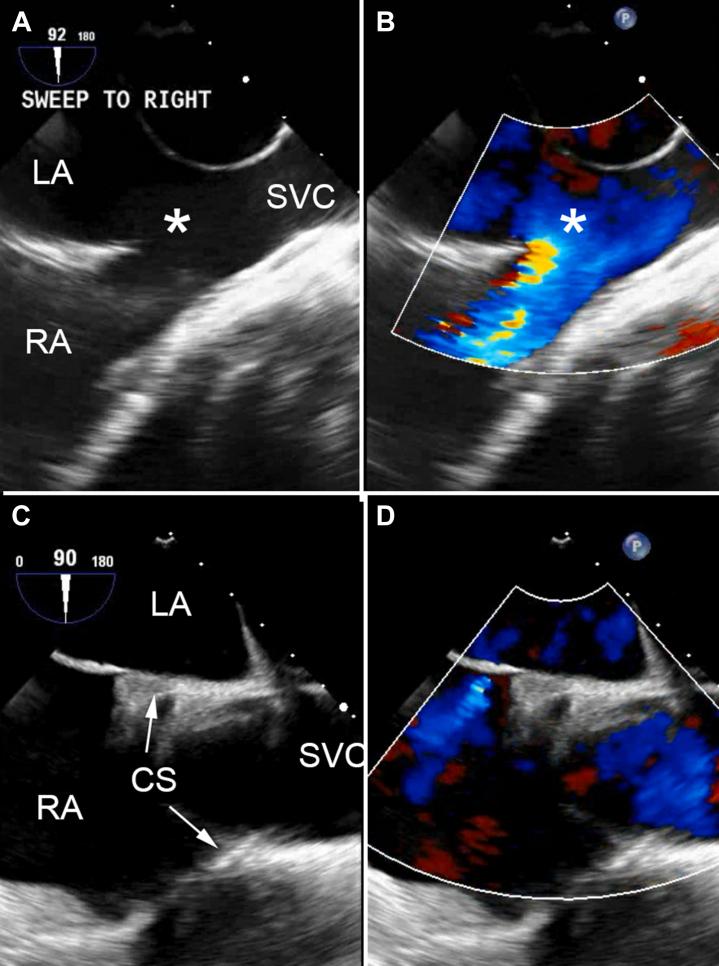

成人先天性心脏病患者的经导管介入治疗

Patients with congenital heart disease now live well into adulthood because of advances in surgical techniques, improvements in medical management, and the development of novel therapeutic agents. As patients grow older into adults with congenital heart disease, many require catheter-based interventions for the treatment of residual defects, sequelae of their initial repair or palliation, or acquired heart disease. The past 3 decades have witnessed an exponential growth in both the type and number of transcatheter interventions in patients with congenital heart disease. With improvements in medical technology and device design, including the use of devices designed for the treatment of acquired valve stenosis or regurgitation, patients who previously would have required open-heart surgery for various conditions can now undergo percutaneous cardiac catheter-based procedures. Many of these procedures are complex and occur in complex patients who are best served by a multidisciplinary team. This review aims to highlight some of the currently available transcatheter interventional procedures for adults with congenital heart disease, the clinical outcomes of each intervention, and any special considerations so that the reader may better understand both the procedure and patients with adult congenital heart disease.

由于外科技术的进步、医疗管理的改善以及新型治疗药物的研发,先天性心脏病患者如今能够很好地活到成年期。随着先天性心脏病患者步入成年,许多人需要通过导管介入治疗来处理残余缺损、初始修复或姑息治疗的后遗症,或后天性心脏病。在过去30年里,先天性心脏病患者经导管介入治疗的类型和数量呈指数级增长。随着医疗技术和器械设计的改进,包括使用用于治疗后天性瓣膜狭窄或反流的器械,以前因各种病症需要接受心脏直视手术的患者现在可以接受经皮心脏导管介入手术。这些手术中有许多都很复杂,且发生在最适合由多学科团队服务的复杂患者身上。本综述旨在强调目前一些适用于成年先天性心脏病患者的经导管介入手术、每种干预措施的临床结果以及任何特殊注意事项,以便读者能更好地理解这些手术以及成年先天性心脏病患者。